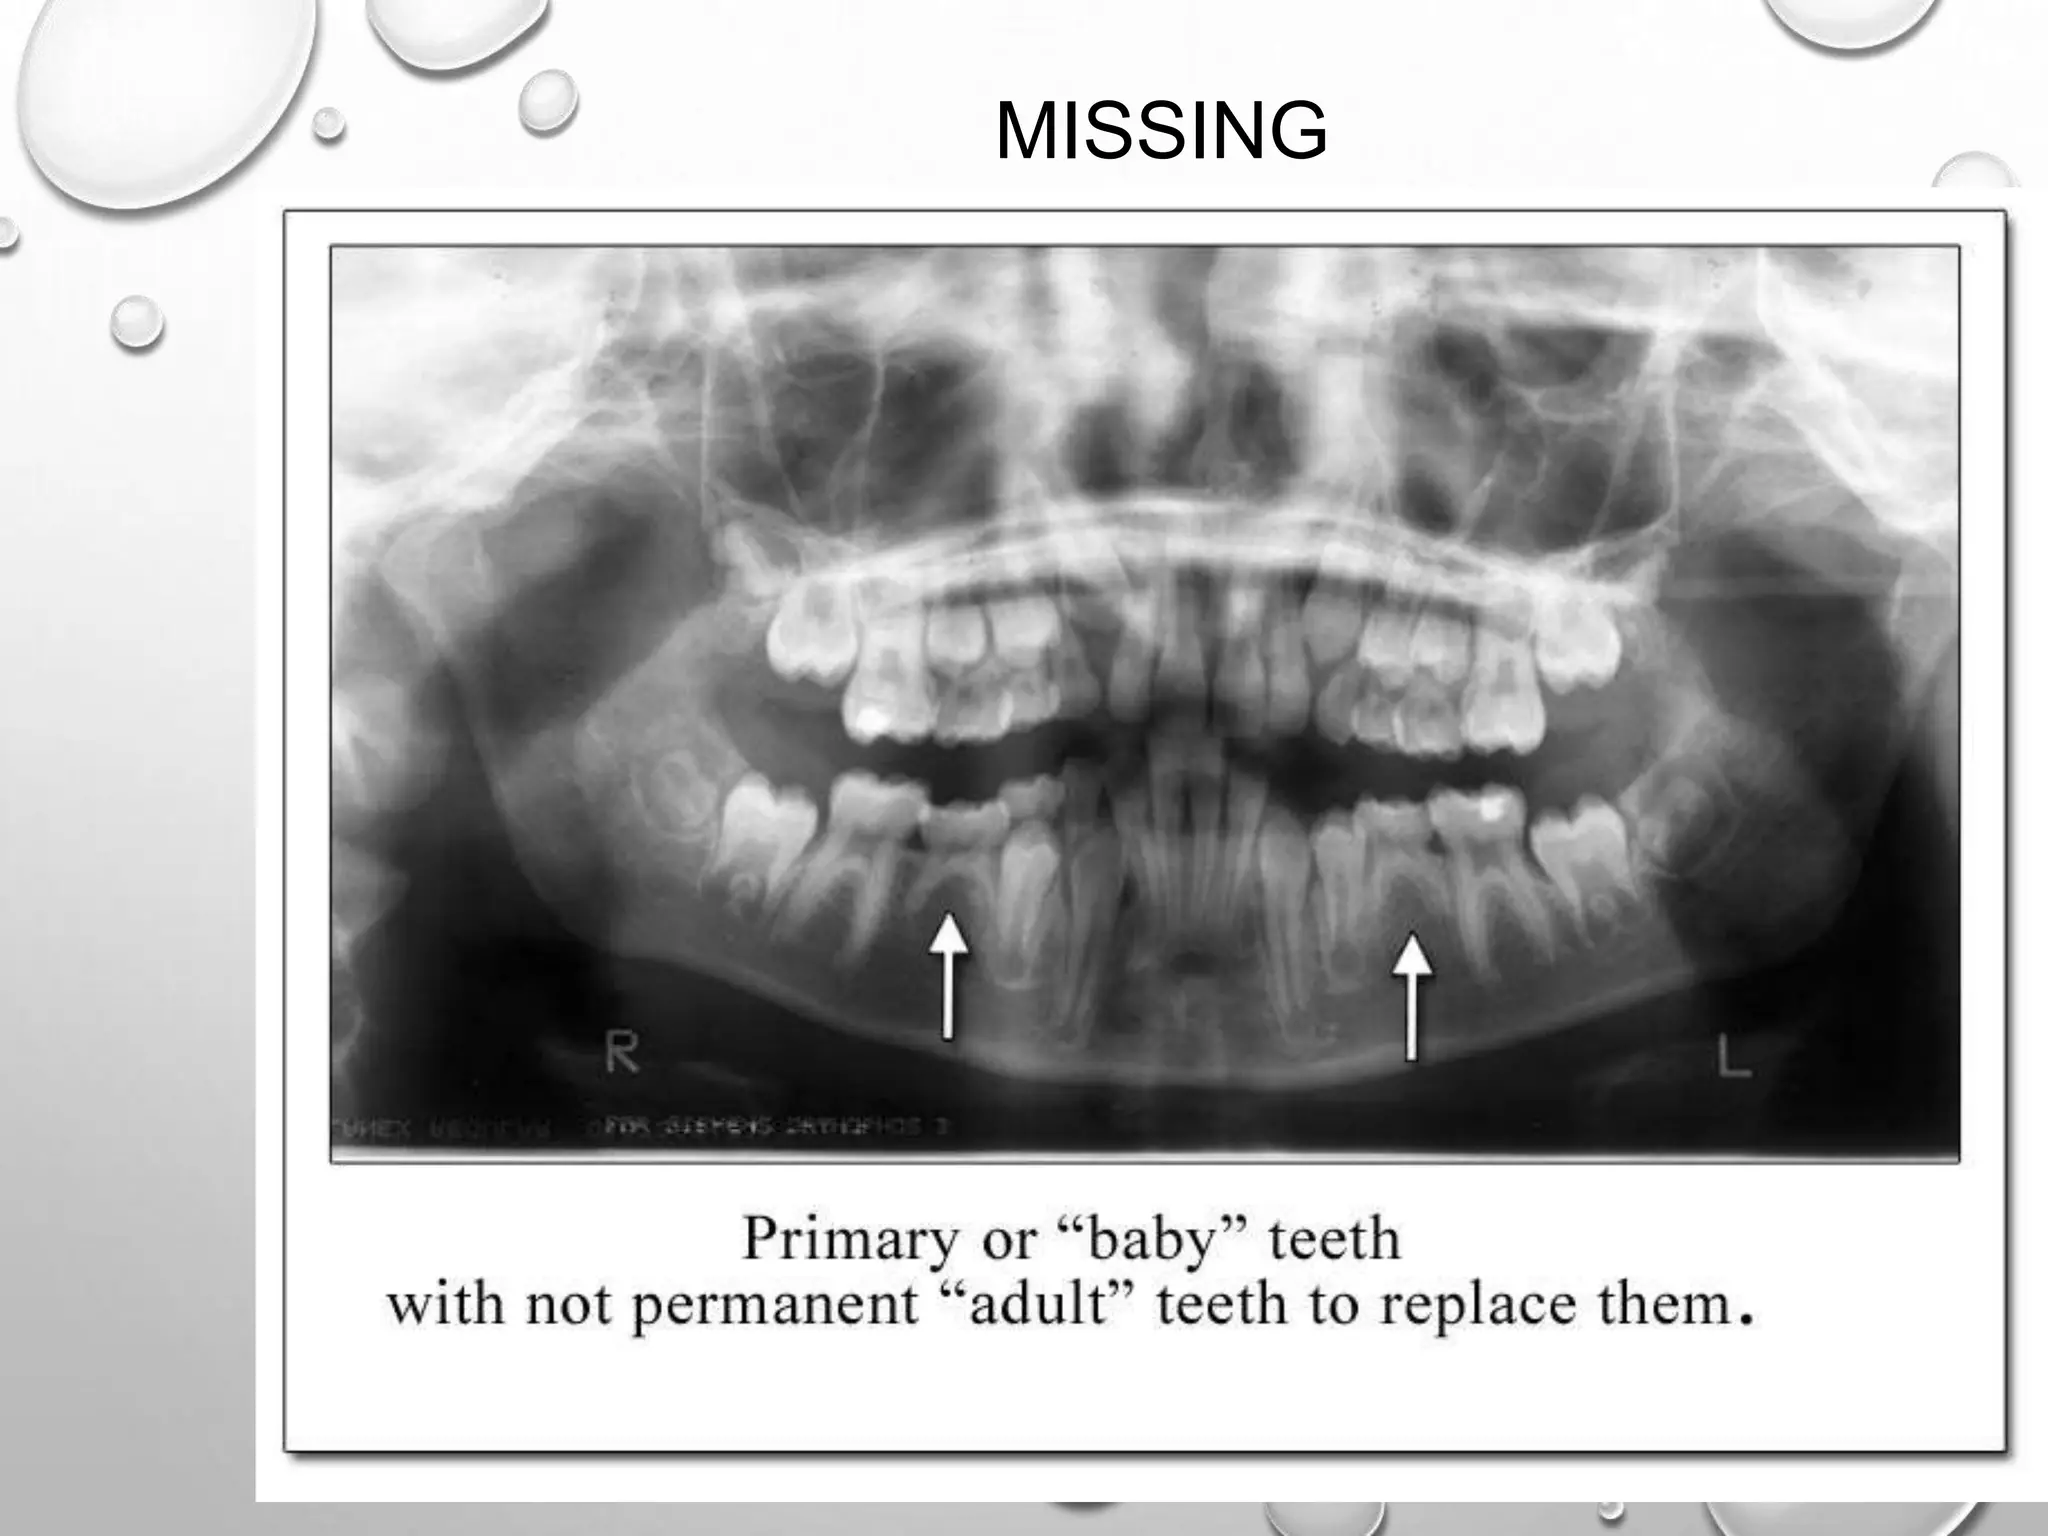

MISSING

PANORAMIC X-RAY ON THIS NINE YEAR OLD

REVEALS CONGENITALLY MISSING ADULT PRE-

MOLAR. YOU CAN SEE ON THE LEFT OF THE

SCREEN THERE IS NO TOOTH BUD FORMING AS

COMPARED TO THE SAME AREA ON THE RIGHT SIDE